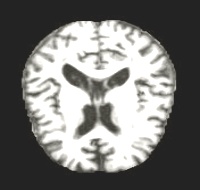

Moderate atrophy

Moderate Dementia

Severe tissue loss

Real MRI scans showing progressive structural brain changes across all dementia stages